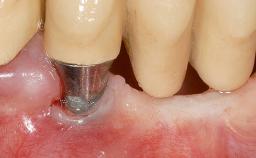

Early Implant Placement, Contour Augmentation, and Autologous Connective-Tissue Graft Using a Tunneling Technique to Replace an Upper Incisor with Generalized Gingival Recession

Variations in soft-tissue volume, evidenced either by an overabundance (Evian and coworkers 1993; Levine and McGuire1997; Dolt and Robbins 1997) or by a deficiency of soft or hard tissue can complicate implant-supported rehabilitations in the esthetic zone (Lorenzana 2008; Lorenzana and coworkers 2009). The present case illustrates the replacement of a failing upper left lateral incisor complicated by generalized severe gingival recession in the esthetic zone.

| Bone Augmentation | Horizontal|Simultaneous |

| Augmentation Materials | Autogenous chips|Xenogenous|Membrane |

| Soft Tissue Grafting | Simultaneous |